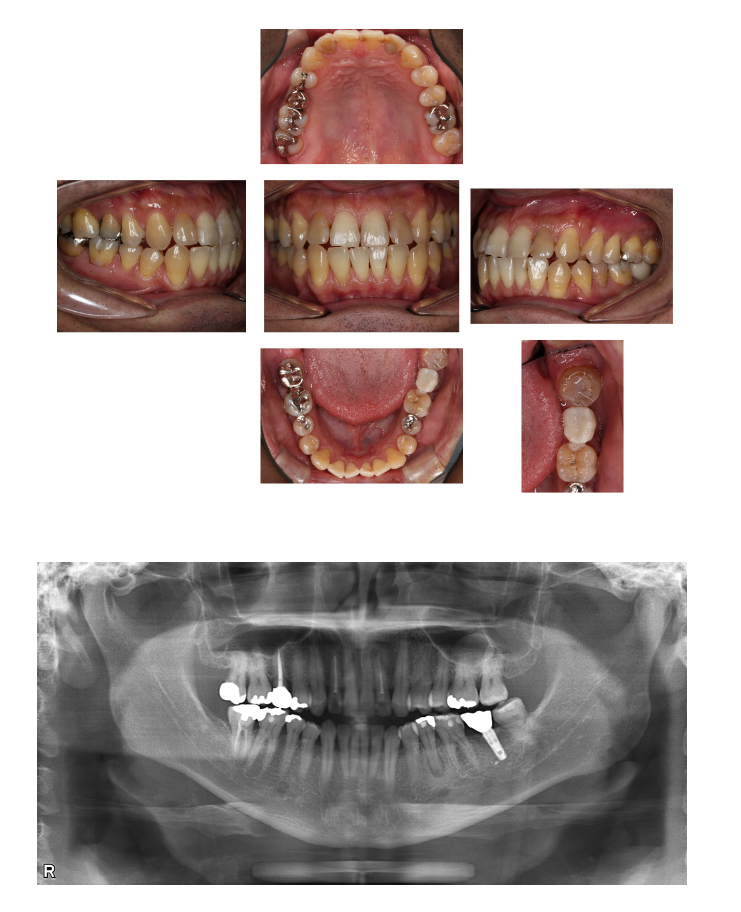

(術前)

年齢・性別:50代 男性

主訴:左下が噛むと痛い

診断:左下第二大臼歯歯根破折

治療内容:インプラント植立

治療期間:7か月

担当医からのコメント:初診時保存不可能で、かぶせを除去して内面が骨の下まで破折を起こしていることを確認。後日抜歯。抜歯直後にリテーナー(仮歯)を装着。5か月待機後インプラントを植立。インプラントを植立して8年経過をしますが、セルフケアも良く、歯肉や骨、噛み合わせに異常がなく経過良好です。メンテナンスも3ヶ月に1回定期的に当院で継続して行っています。